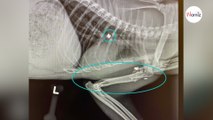

Grave incidente a Marino nel tardo pomeriggio di ieri coinvolto un giovane di 16 anni che si trovava alla guida di una microcar. L’incidente, avvenuto sulla via Nettunense, si è verificato nelle vicinanze del distributore di carburante in località Castelluccia. Il giovane ha riportato gravi fratture e un vasto ematoma e, dopo essere stato portato in codice rosso all’ospedale dei Castelli Romani, è stato trasferito d’urgenza al Bambino Gesù di Roma. Lo scontro frontale ha coinvolto la minicar in cui viaggiava il sedicenne e una Mercedes, entrambe ridotte a lamiere contorte. Il conducente della Mercedes ha subito ferite, seppur meno gravi di quelle riportate dal giovane al volante della microcar. Sul luogo sono intervenuti immediatamente gli agenti di polizia locale del comando di Marino, insieme a un’ambulanza del 118. Il traffico è rimasto bloccato per ore sulla via Nettunense e sulla via Appia, con forti rallentamenti in entrambe le direzioni fino a tarda sera.